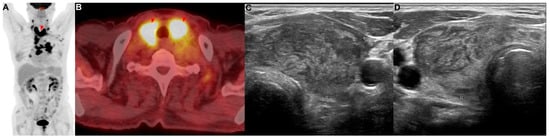

A 77-year-old man with a medical history of diabetes mellitus was referred for an abnormal chest radiograph, which was taken at a public health clinic. He had a history of 57 pack years of smoking. He stated that he did not take any medications or have any illnesses, including cardiovascular, allergic, rheumatic, or respiratory conditions. A contrast-enhanced CT scan of the chest showed a lung mass invading a lobar bronchus of the left upper lobe. A bronchoscopic biopsy was performed and squamous cell carcinoma was diagnosed. If there was no metastasis, the tumor was considered stage IIIC as T4N3. There was no suspicious finding of distant metastasis except for a hypermetabolic lesion (SUVmax = 13.42) of the bilateral lobes of the thyroid gland in PET/CT (Figure 2A,B). FNA and cytology were performed on the lesion of the left thyroid gland (Figure 2C,D), and metastasis of squamous cell carcinoma was confirmed (Figure A1B). This patient was treated with six courses of platinum-based chemotherapy (gemcitabine and cisplatin) for stage IV squamous cell carcinoma.

Figure 2. Patient 2: a 77-year-old man diagnosed with squamous cell carcinoma of the lung with metastases in the thyroid. (A,B) PET/CT showed metastatic lesions (red arrowhead) in the bilateral lobes of the thyroid. (C,D) Metastatic lesions were observed in the (C) left and (D) right thyroid.